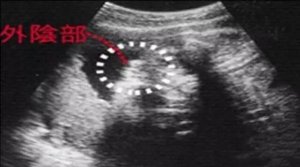

[生男生女]B超看胎儿性别是最科学,也是最准确的方法。通过四维彩超可以知道胎儿性别,我国禁止性别鉴定。尽管大家都知道如今国家有明文规定,任何医疗机构、任何医护人员,都不得以任何方式向